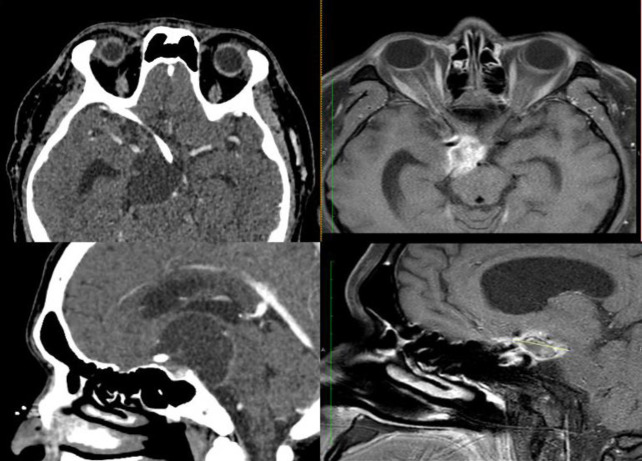

Craniopharyngioma is a rare, benign intracranial tumour that can present with solid, cystic, or mixed solid-cystic characteristics. This case report aims to discuss the follow up assessment of our patient after one year of the irradiation therapy for craniopharyngioma. A 43-year-old male who has underlying refractory cystic craniopharyngioma requiring two-weekly aspirations, complicated with visual impairment and panhypopituitarism, was referred to our department for intra-cavitary irradiation therapy. Initial diagnostic assessment with Tc-99m MAA followed by dose calculation using the Backlund formula were conducted prior to the therapy. The patient received 6.22 mCi (230.14 MBq) of Ytrrium-90 citrate colloid via the Ommaya reservoir to deliver a radiation dose of 300 Gy to the tumour. Positive outcomes were observed as signified by the reduction on the aspirated cystic frequency and volume, tumour volume, improvement on the visual function and stable hormonal level. Despite the complications, the intra-cavitary irradiation therapy has demonstrated a significant and valuable therapeutic option for our patient in the management of refractory cystic craniopharyngioma.